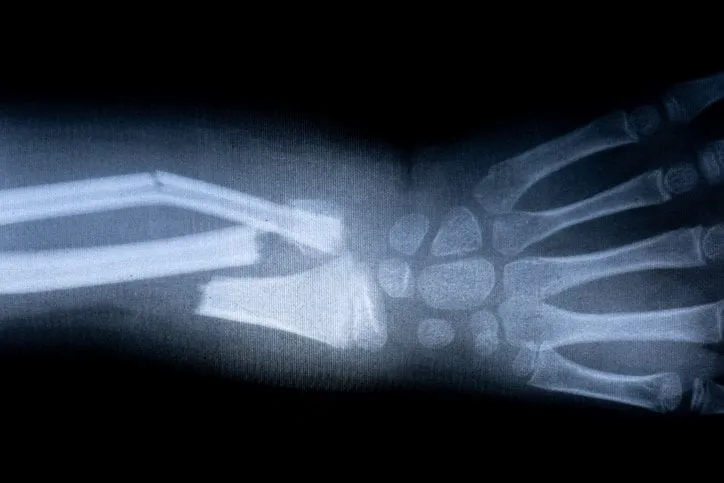

Os fragiles

6/17

x-ray film skeleton human arm health medical anatomy body concept

Istock

En cas de carence en vitamine D, les os peuvent devenir plus fragiles. Ceux de la colonne vertébrale, du bassin et des jambes sont particulièrement touchés. Le risque de fracture devient plus important.